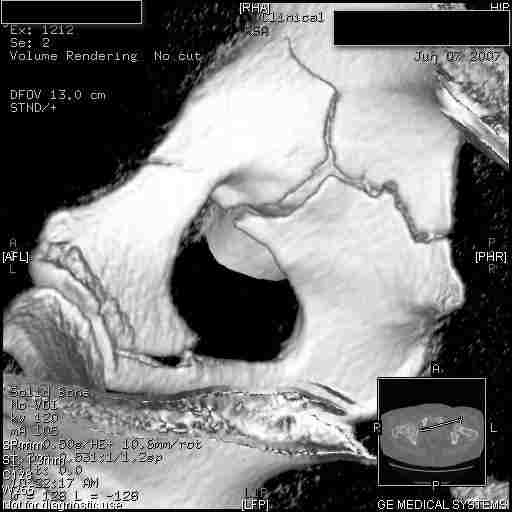

Следом 3d

Приветствую,Антон.Рункова рядом нет,но после полученных данных КТ,обсуждали совместно.Итог обсуждения-развернутый ответ дать не получится,т.к.срезы выбраны не информативные.Если ориентироваться на данные 3D,то ,ИМХО,можно лечить на вытяжении.